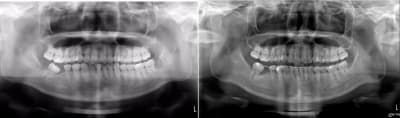

Suivis à 3 mois.

Encore un mois a priori.

Et un autre cas 5 semaines d'interval entre les deux photos.

Enfin là j'ai seulement à ouvrir les espaces pour les implants.